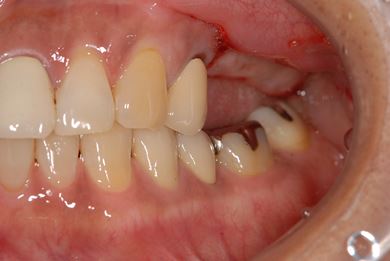

骨再生インプラント治療+セラミック治療+歯肉歯槽骨整形手術

| 主訴 | 左奥上の歯ぐきの痛みの治療相談。 | ||||||||||||||||||||||||||||||||

| 治療内容 | インプラント2本(ソケットリフト、GBR)、メタルボンドセラミッククラウン3本、歯肉歯槽骨整形手術 | ||||||||||||||||||||||||||||||||